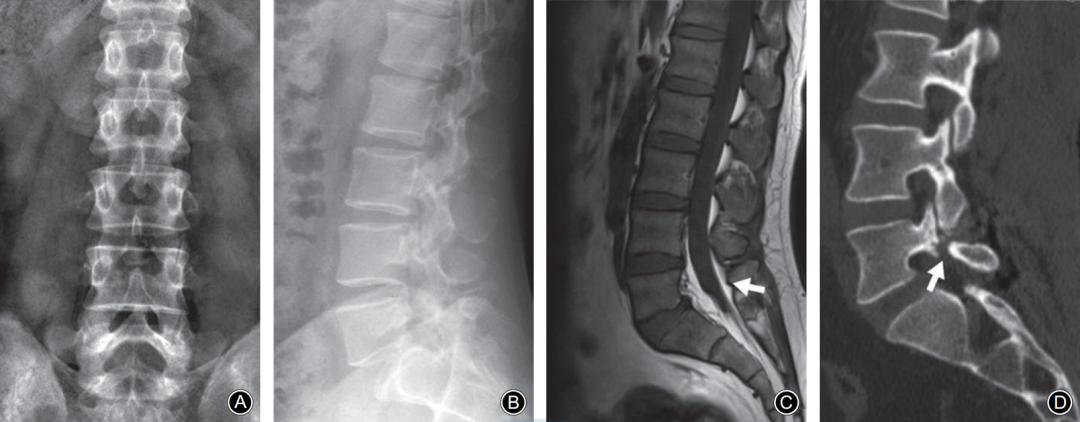

L5椎弓峡部裂典型病例一:男,32岁。A,B: 腰椎正位侧位X线片示无明显椎弓峡部裂征象; C: 腰椎 MRI正中矢状面T1WI示L5棘突基底部与硬膜之间出现脂肪高信号带(箭头示); D: 腰椎CT矢状面重建示L5椎弓峡部骨质不连(箭头示)。

L5椎弓峡部裂典型病例二:男,35岁。A,B: 腰椎正位侧位X线片均无明显椎弓峡部裂征象; C: 腰椎MRI正中矢状面T1WI示L5棘突基底部与硬膜之间出现脂肪高信号带(箭头示); D: 腰椎CT矢状面重建示L5椎弓峡部骨质不连,裂隙较细(箭头示)。